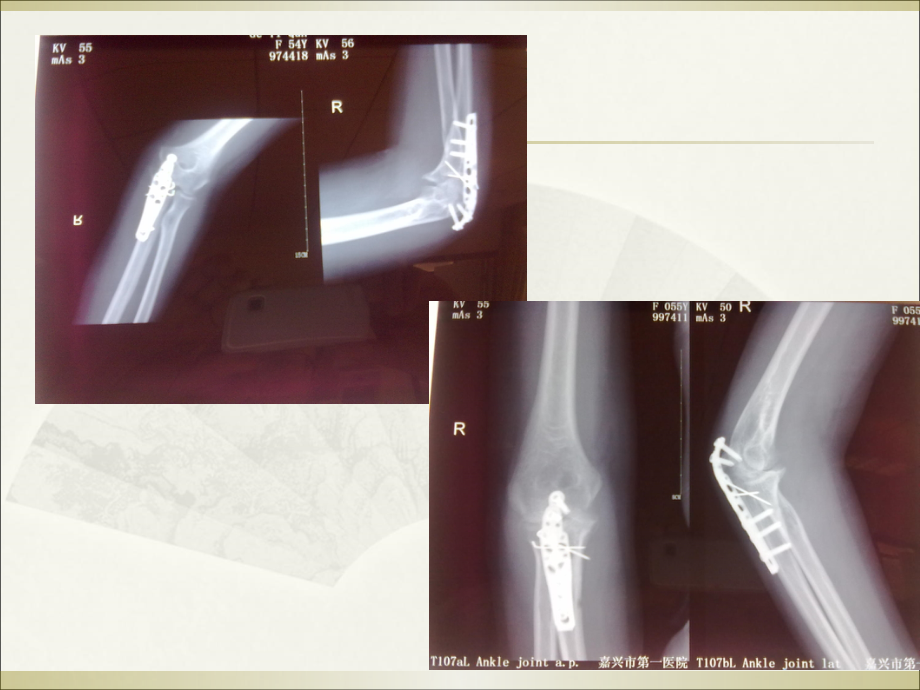

,单击此处编辑母版标题样式,单击此处编辑母版文本样式,第二级,第三级,第四级,第五级,*,*,单击此处编辑母版标题样式,单击此处编辑母版文本样式,第二级,第三级,第四级,第五级,*,*,单击此处编辑母版标题样式,单击此处编辑母版文本样式,第二级,第三级,第四级,第五级,*,*,单击此处编辑母版标题样式,单击此处编辑母版文本样式,第二级,第三级,第四级,第五级,*,*,单击此处编辑母版标题样式,单击此处编辑母版文本样式,第二级,第三级,第四级,第五级,*,*,单击此处编辑母版标题样式,单击此处编辑母版文本样式,第二级,第三级,第四级,第五级,*,*,单击此处编辑母版标题样式,单击此处编辑母版文本样式,第二级,第三级,第四级,第五级,*,*,单击此处编辑母版标题样式,单击此处编辑母版文本样式,第二级,第三级,第四级,第五级,*,*,单击此处编辑母版标题样式,单击此处编辑母版文本样式,第二级,第三级,第四级,第五级,*,*,单击此处编辑母版标题样式,单击此处编辑母版文本样式,第二级,第三级,第四级,第五级,*,*,单击此处编辑母版标题样式,单击此处编辑母版文本样式,第二级,第三级,第四级,第五级,*,*,关节挛缩的概述,肌肉能量技术,治疗方法,机制,肘关节,ROM(30,130),可完成,90%,以上的日常动作,肘关节的活动度约占上肢运动功能的,70%,屈伸活动占肘关节功能的,60%,占上肢功能的,42%,创伤后韧带和肌腱的病理学变化,致密结缔组织(,正常,肌腱、韧带),肉芽组织(,2-3,天,出现),肉芽组织机化(,2,周后,出现),瘢痕组织(,3,个月,后),兔膝关节固定,2,周对关节功能影响有限,而当固定延长到,6,周时,关节发生严重的挛缩。固定时间在,8,周以内时,随固定时间延长,关节功能快速丧失,超过,8,周以后关节功能丧失缓慢。,卢国强,.,创伤后的关节挛缩,J.,中国组织工程研究,,2012,16:7345-7349.,制动会导致肌膜的胶原纤维发生改变,使肌膜硬化、弹性下降。由于肌膜的限制作用,将会使整块肌丧失其伸展性,造成肌性挛缩。,长期制动,关节囊,挛缩和增厚,侧副韧带,挛缩,肌肉、肌腱,等,软组织,挛缩,软组织挛缩,挛缩定义:,肌腱装置和通过关节周围的软组织适应性短缩,导致被动或主动牵伸明显的抵抗和限制,ROM,。,关节牵引,肌力训练,软组织松动术,关节挛缩,关节外,关节内,挛缩,粘连,粘连 附属运动,关节松动术滑动,牵伸训练,石膏固定、手术,康复技术线路图,牵伸概述,牵伸或称牵张、牵拉,是指拉长挛缩或短缩软组织的治疗方法。,目的:改善或重建关节周围软组织的伸展性,/,降低肌张力,/,改善,ROM/,防止不可逆组织挛缩,/,预防或降低肌肉肌腱活动时损伤。,与牵引(,traction,)区别:牵引主要作用与关节,通过力学原理增大关节间隙。,肌肉牵拉技术分类,被动牵拉,手法被动牵拉,机械被动牵拉,主动抑制,收缩,-,放松,收缩,-,放松,-,收缩,拮抗肌收缩,自我牵拉,肌肉能量技术(,MET,),肌肉能量技术,肌肉能量技术,(Muscle Energy Techniques,MET),亦称为等长收缩法,是针对软组织、肌肉、骨骼系统紊乱,由操作者精确控制方向和施力大小,通过患者的主动参与、利用肌肉等长或等张收缩抗阻的方式,用以改善肌肉骨骼系统功能和减轻疼痛的一类操作技术。,Kabat,在,20,世纪,40,年代创立了,MET,,同时他将这种技术也命名为本体感觉神经肌肉易化,(PNF),在,20,世纪,50,年代,Fred.Janda,在此基础上进行了改良,使,MET,疗效得到了进一步提高,Voss D,Ionta M,Myers B.Proprioceptive neuromuscular facilitation.Philadelphia:Harper and Row,1985.125.,休德里克逊,编著,.,叶伟胜,万瑜,译,.,骨科疾病的矫形按摩,.,天津,:,天津科技翻译出版公司,2004.4-5,51-56.,肌肉的物理特性,伸展性,:肌肉放松受外力牵拉长度增加的特性,弹性,:外力消失时肌肉又恢复到原来的形状,粘滞性,:肌肉活动时由于肌肉内部的粘滞性,构成肌肉拉长与回缩时的内阻力。,肌肉的物理特性受温度的影响。当肌肉温度升高时,肌肉的粘滞性下降,伸展性和弹性增加。,肌肉的物理特性,粘弹性,特性,弹性形变,塑性形变,蠕变,应力松弛,弹性形变,是指随外力的撤去,而逐渐消失的那种形变,。,塑性形变,是指外力撤去后,组织所遗留的不能消失的那部分形变。,蠕变,(creep),是指软组织突然受到应力的作用,此后保持此应力不变,软组织将继续产生形变的现象。,应力松弛,(stress relaxation),是指软组织突然发生形变,然后保持此长度不变,软组织内应力随时间而逐渐减少的现象。,损伤愈合过程及牵拉时机,炎症期(红肿热痛)禁忌牵拉,增生期(,521,天),1621,天牵拉有效,重塑期(第,21,天始)不继续进行牵拉可能致挛缩,MET,方法,收缩,-,放松技术,保持,-,放松技术,肌肉牵拉基础,高尔基腱器:位于肌肉,-,肌腱结合处,是接受牵拉刺激的感受器。,快速牵拉肌肉时,:肌梭兴奋,刺激传入神经纤维,增加肌张力,这一过程称为单突触牵拉反射。,缓慢持续牵拉肌肉时,:高尔基腱器兴奋,激发抑制反应,使肌肉张力降低,肌肉放松,长度变长。,因此,进行牵拉时,,牵拉的速度,、,强度,和,持续时间,将影响到治疗效果,牵伸的作用机制,相关反射,肌肉牵张反射:,骨骼肌中肌梭感知肌肉的过度拉长而产生保护性反射。,逆牵张反射,(,即主动抑制,),,张力感受器腱梭,一般认为若负荷相对变大,腱梭被激活,通过神经性抑制可引起肌肉的依次放松。,交互抑制,:Sherrington,认为当肌肉收缩时,通过交互抑制将抑制拮抗肌,允许关节发生运动。,Ballantyne,等研究,MET,技术对于腘绳肌延展性机制中发现腘绳肌等长收缩,5s,相比于,20s,,其,延展性改善更明显,。,在相同次数的治疗时间里,牵拉,30s,的效果比牵拉,15s,的效果明显,但与牵拉,60s,相比未见显著性差异。,Ballantyne F,Fryer G,McLaughlin P,et al.The effect of muscle energy technique on hamstring extensibility:themechanism of altered flexibilityJ.J OsteopathMed,2003,6:59-63.,Bandy WD,Irion JM.The effects of time on static stretch on the flexibility of the hamstring muscleJ.Phys Ther,1994,74:845-852.,使用,20%,、,60%,和,100%3,种不同最大等长收缩力量,其研究结果未见显著性差异,Feland JB,Marin HN.Effect of sub maximal contraction intensity in contract-relax proprioceptive neuromuscular facilitation stretchingJ.Br J Sports Med,2004,38(4):18.,适应症,降低张力过高的肌肉张力,增加受限关节的活动范围,帮助感觉和运动的整合,软组织挛缩、粘连或疤痕形成,禁忌症,关节内或关节周围组织有炎症(如结核、感染,特别在急性期),新近发生的骨折,新近发生的肌肉、韧带损伤,组织内有血肿或有其他创伤体征存在,神经损伤或神经吻合术后一个月内,注意事项,避免过度牵拉,避免过度牵拉已长时间制动或不活动的肌肉结缔组织,避免牵拉水肿组织,避免过度牵拉肌力较弱的肌肉,牵拉不应引起剧烈疼痛,关节活动或肌肉被拉长时有剧痛,严重的骨质疏松,慎重:为了维持关节的稳定性或为了使肌肉保持一定的力量,增加功能活动的基础,如,SCI,、肌肉严重无力的患者。,肘关节屈曲时,前臂旋前、旋后等主要的作用肌肉不同,在牵伸时需要区分?,参考文献:,麦明泉,林彩娜,伍少玲,等,.,肌肉能量技术治疗膝关节骨性关节炎疗效,.,中国医疗前沿,2012,7:9395.,阿诺德,尤卡 著,刘润芝译,.,牵伸解剖指南,M,北京体育大学出版社,,2008.,陈方灿主编,.,运动拉伸实用手册,M,北京体育大学出版社,2008.,Leon Chaitow.Muscle Energy TechniquesM.Harcourt Publishers Limited,2001.,里克特,亨琴编赵学军,等,.,肌肉链与扳机点:手法镇痛的新理念及其应用,M,山东科学技术出版社,2011,:,96-100.,Thank you!,